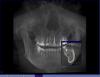

libertytower Опубликовано 18 июля, 2011 Автор Поделиться Опубликовано 18 июля, 2011 (изменено) Сняли лекарство, два раза ставили противовоспалительное что-то. Боль не утихает (режущая пульсирующая, очень сильной интенсивности). Обезболивающие работают максимум на половину от срока действия. Кетанов купирует боль неполностью.При промывании каналов гноя практически нет.Прилагаю копию из томограммы где видно гранулему(еще ДО врачебного вмешательства). Пожалуйста, подскажите кто-нибудь, грамотный эндодонтист, от чего боль очень сильной интенсивности не спадает? Что делать в моей ситуации?Терпеть настолько сильную боль больше нет сил... Изменено 18 июля, 2011 пользователем libertytower Ссылка на комментарий

Scrabble Опубликовано 18 июля, 2011 Поделиться Опубликовано 18 июля, 2011 Какой зуб лечите? Если 37, там очень похоже на трещину... Ссылка на комментарий

libertytower Опубликовано 19 июля, 2011 Автор Поделиться Опубликовано 19 июля, 2011 Зуб 7-й, к сожалению не знаю какая часть 3-я. Нижний.Скорее всего буду удалять и ставить имплант. Перед этим хотел бы убедиться что сделать совсем ничего нельзя. Предположение что есть трещина - есть. Посмотрите, пожалуйста, еще снимок. Возможно ли что данное воспаление давит на нерв?Еще хотелось бы узнать можно ли делать при периодонтите одновременную замену на имплант? Или это является противопоказанием? Ссылка на комментарий

Scrabble Опубликовано 19 июля, 2011 Поделиться Опубликовано 19 июля, 2011 Совершенно очевидно, что между полостью апикального процесса и нижнечелюстным каналом есть кость, так что ничего никуда не давит. По поводу одномоментной имплантации спросите в разделе хирургии-я тут не спец. Предполагаю всё же, что не надо, да и зачем? Во фронте-понятно, а здесь? Ссылка на комментарий